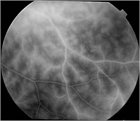

1. 滲出型加齢黄斑変性(AMD)に対する抗VEGF薬治療の維持期管理では、OCTによる検査結果をもとに再投与の判断を行ってよい。フルオレセイン蛍光眼底造影検査は必ずしも必要ない(推奨度1)